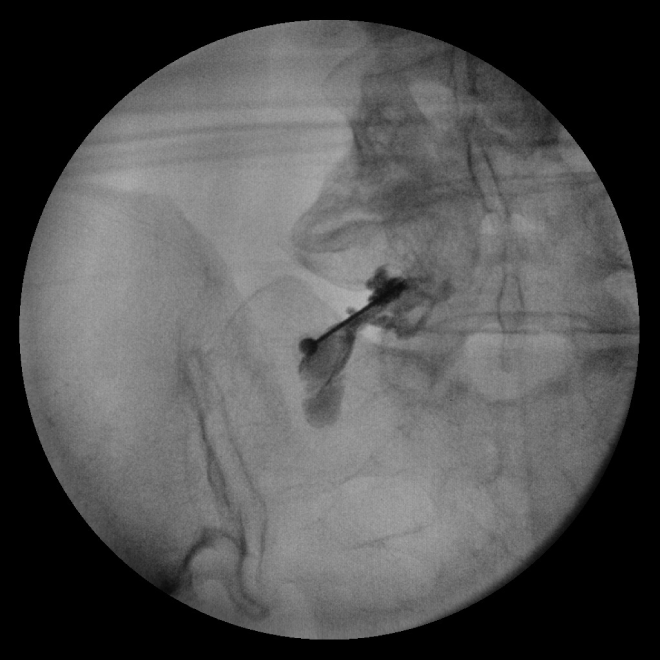

신경차단술(블록)

신경 주위에 약물을 주입하여 염증과 부종을 가라앉혀 통증을 완화시키는 시술입니다.

실시간 고해상도 영상장비 C-arm을 확인하며 통증의 원인이 되는 부위에 직접 약물을 주입해

신경이 눌려 발생하는 요통이나 디스크 등 척추 관절 통증 치료에 효과적입니다.

신경차단술 치료 적응증

□ 목, 허리 디스크

□ 척추관협착증

□ 만성요통

□ 척추측만증, 척추분리증

□ 척추 수술 후 통증이 있는 경우

□ 대상포진 및 대상포진 후 신경통